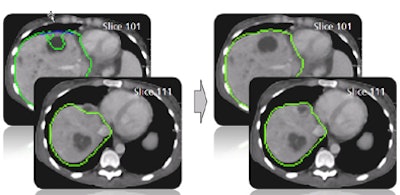

![]() |

| The results demonstrate correction of the segmentation in 3D in the user-selected 2D slice, as well as automatic correction in the adjacent slices. |

| In step two, morphological postprocessing ensures a coherent, smooth mass. The opening process removes small artifacts, connected component analysis removes separated parts, and closing eliminates small gaps. |